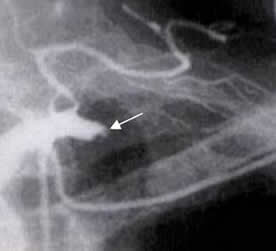

Fig 142 B. Trauma vascular.

Angiografía. Oclusión de la arteria subclavia izquierda, como complicación de una herida con arma cortopunzante, a nivel supraclavicular.